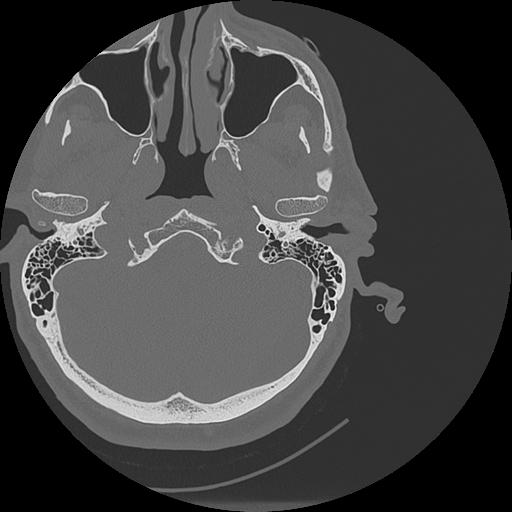

7 HUESO,,Vol,0.5,HUESO,,